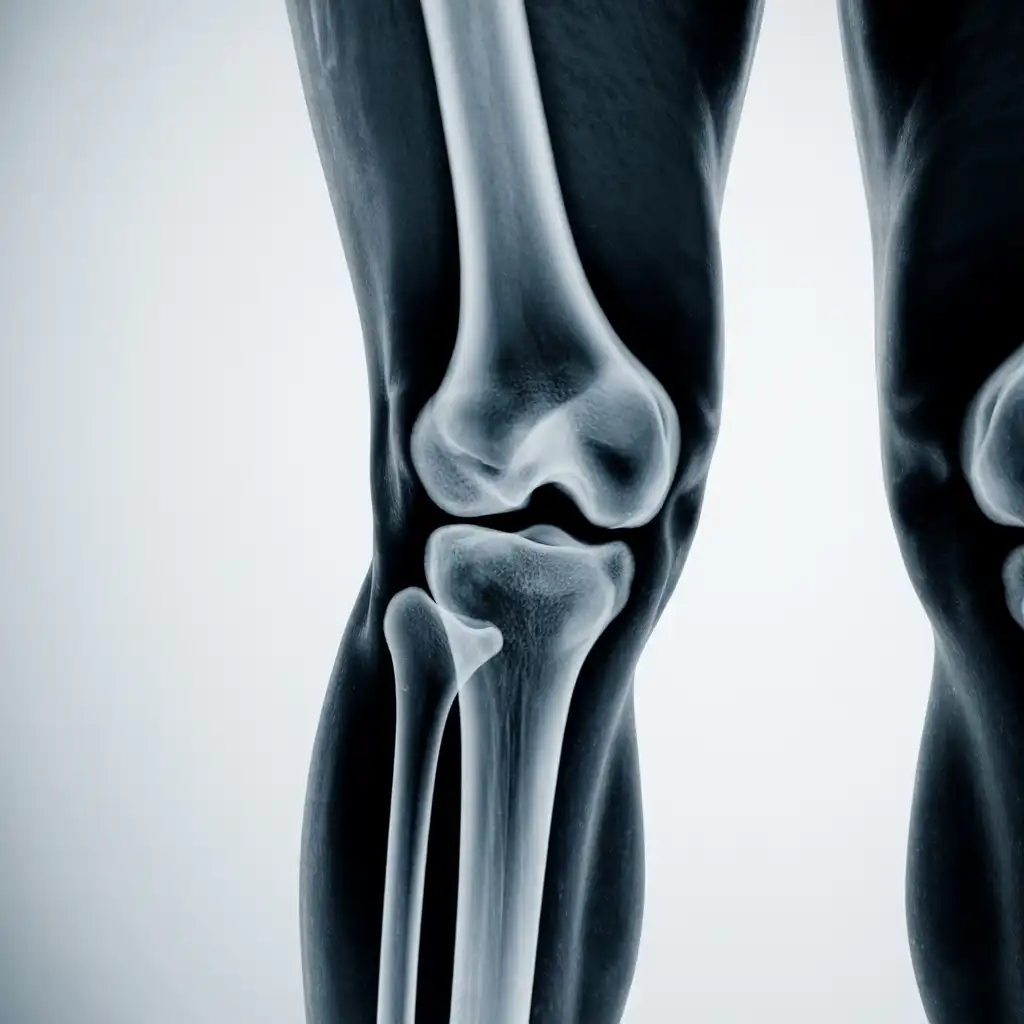

Una radiografia a domicilio è un esame radiologico eseguito da un tecnico specializzato che viene a casa tua con apparecchiature digitali portatili. L’esame si svolge sul posto, senza spostare il paziente e con la stessa qualità di una struttura ospedaliera.

Dopo l’acquisizione delle immagini, queste vengono inviate al medico radiologo che referta rapidamente e ti invia tutto in formato digitale. Un servizio comodo, sicuro e ideale per chi ha difficoltà negli spostamenti.